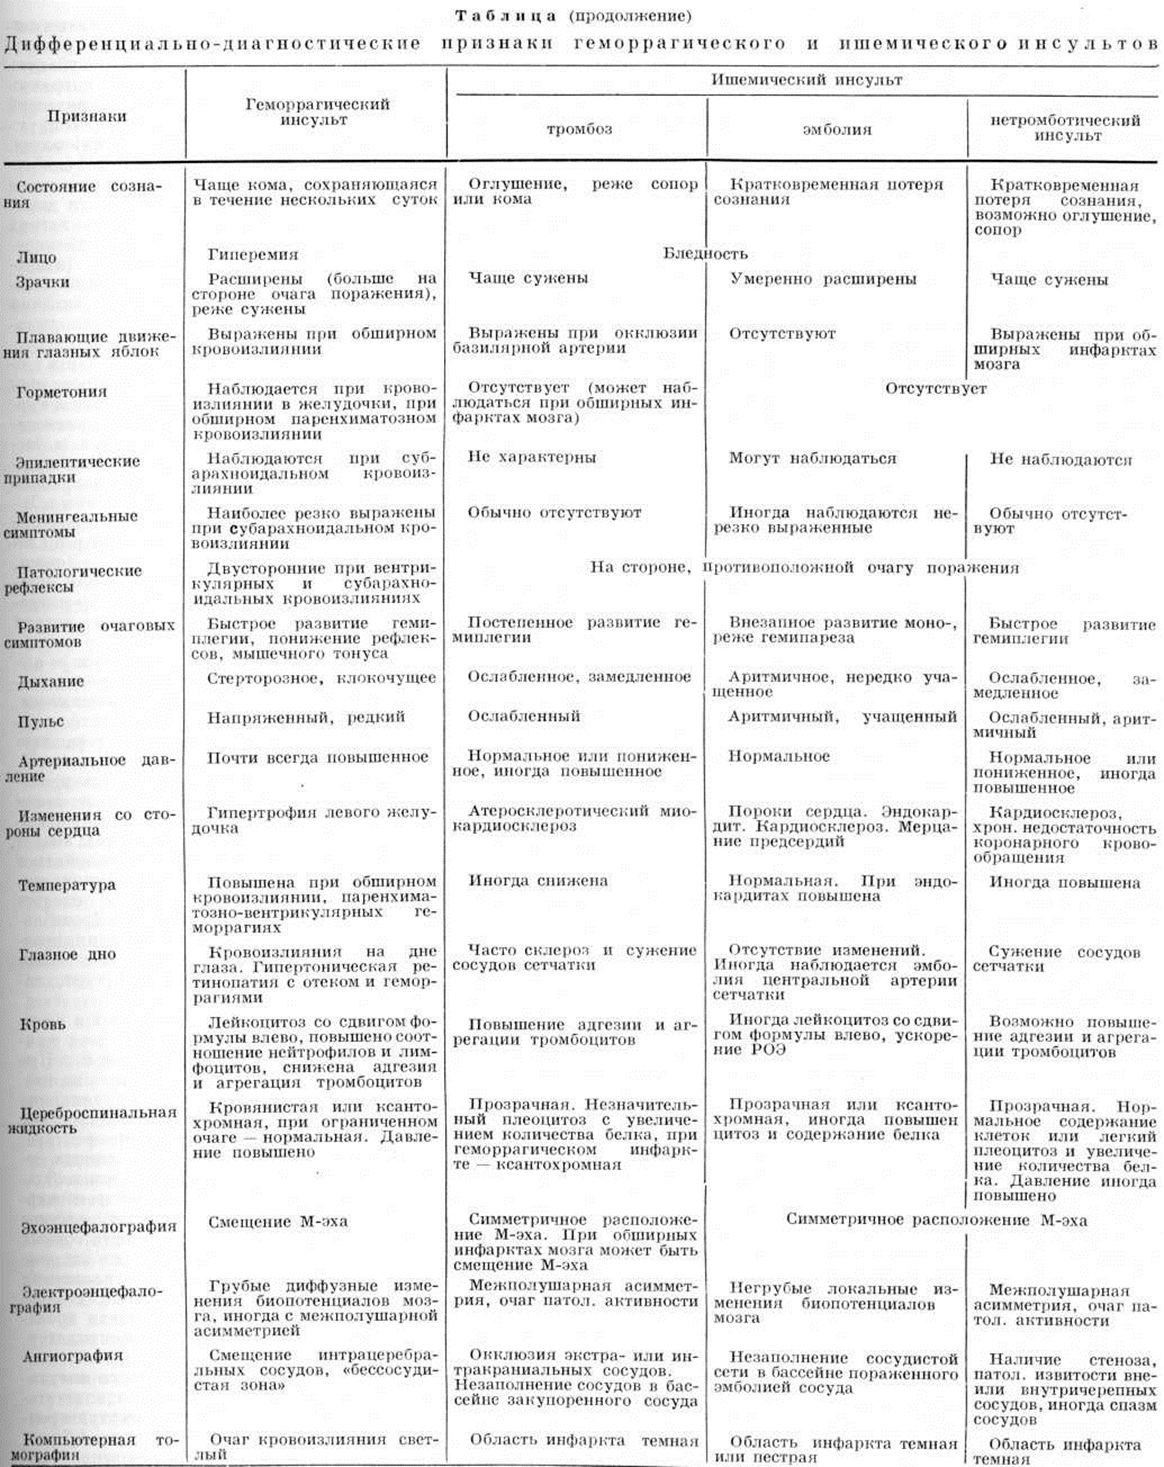

Дифференциальная диагностика геморрагического и ишемического Инсульт — смотри полный свод знаний таблицу.

| ||

| ||

| ||

| ||